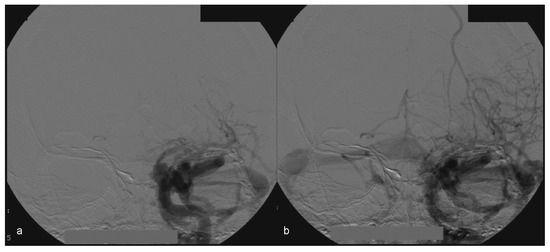

Figure 8.

(a, b) Left side angiography, with coronal view, showing congestion toward the left orbit.

Examination of the patient showed normal results on the right side (Figure 7). The left side displayed significant alterations (Figure 8). It showed Type A CCF.